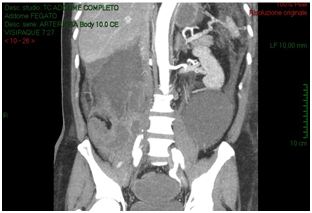

The CT-scan, targeted to a suspect of hemorrhage, did not have delayed phases. Patient received paracentesis with around 3200 cc fluid drained that was sent to microbiological examination. Result of bacteriological exam revealed infection by Proteus Mirabilis and he received target antibiotic therapy with resolution of septic status. In XXII post-operative day, for a progressive increase of serum creatinine we decided to perform an Uro-CT scan. The exam showed reduction of intraperitoneal fluid, right iliac side fluid collection with contrast enhancement during delayed phases; right ureter was not visible under fluid collection (Figure 3). We attempted to insert a ureteral stent in retrograde way but ureter resulted totally interrupted inside the fluid collection so the patient was undergone to explorative laparotomy and toilette of fluid collections. We found ureteral loss of substance of around 3 centimeter localized in anterior ureteral wall. We manufactured end-to-end ureteral anastomosis after positioning of ureteral stent seven French. We removed ureteral stent after 3 months and currently the patient is in follow-up with a good renal function as shown at last CT-scan after 10 months (Figure 4).

Figure 2: CT-scan shows increasing of intra-retroperitoneal fluid with small bowel and right colon compression and increase of right iliac region serous-hematic fluid.